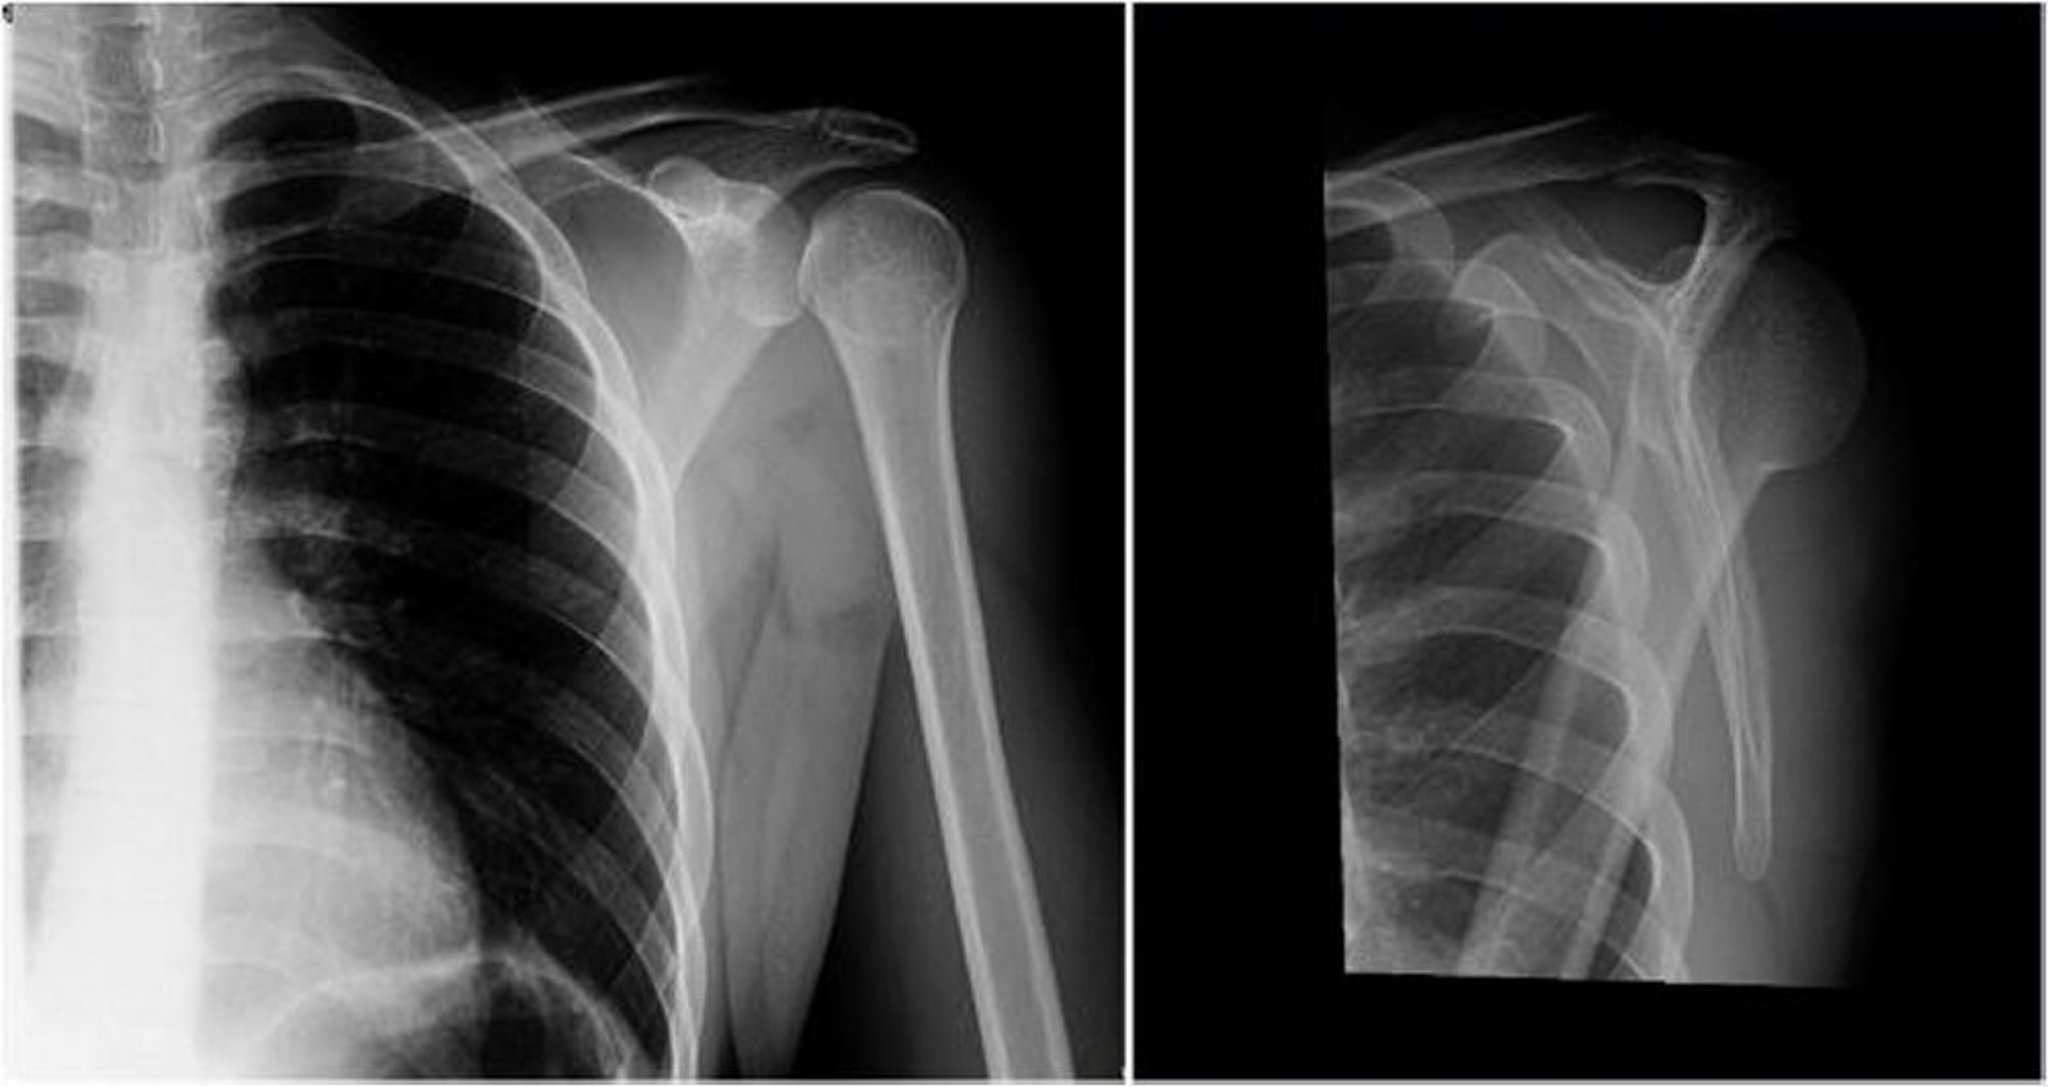

Hintere Schulterluxation: Anteroposteriore und Y-Ansicht

Im linken Bild (anteroposteriore Ansicht) ist der Humeruskopf nach innen gedreht, was zu dem Glühbirnen- oder Eistüten-Zeichen führt (Vorsprünge der Tubercula humeri majoris und der Tubercula minoris sind nicht zu sehen), was auf eine hintere Luxation hinweist. Im rechten Bild (Y-Ansicht) liegt der Humeruskopf hinter der Fossa glenoidalis, was auf eine posteriore Luxation hinweist.

Image courtesy of Danielle Campagne, MD.